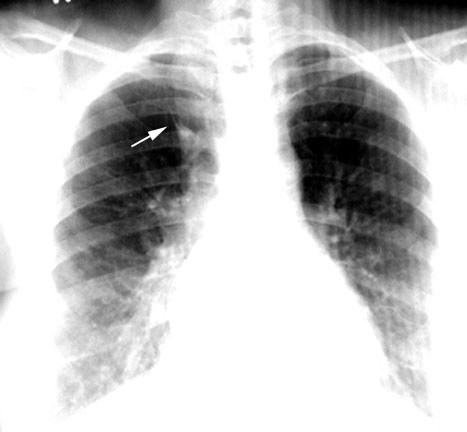

Azygous Lobe

• Inverted comma sign

See labeled image below.

Inverted comma sign